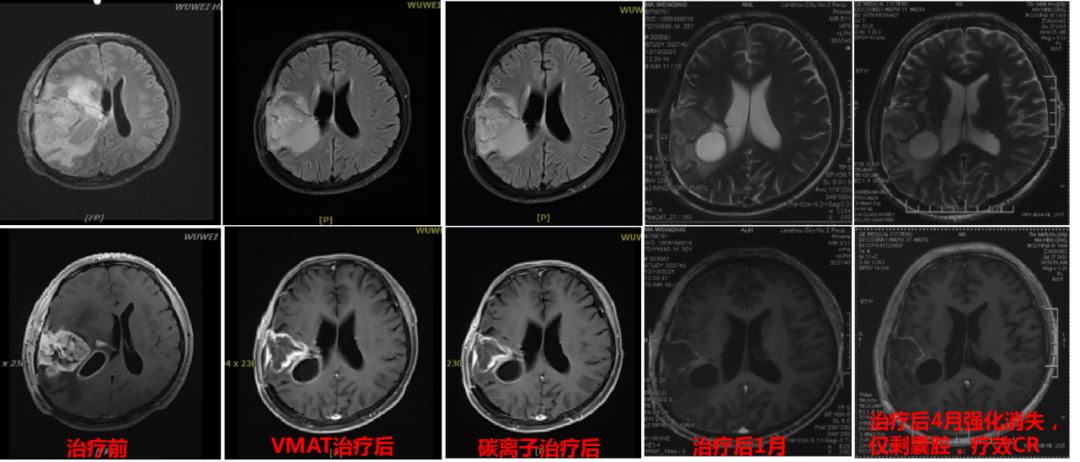

2019年,42岁的杨女士不幸被脑胶质瘤“击中”,犹如晴天霹雳一般,辗转多家医院后在天坛医院确诊为脑胶质瘤,因位置特殊,无法进行手术切除。得知这个消息后杨女士心情低落,寻求最佳治疗方法。2020年5月,杨女士多次出现癫痫,复查后得知肿瘤较前增大,脱水、抗癫痫治疗后症状仍不能缓解。不能做手术,肿瘤长在脑袋里面就像一个定时炸弹,杨女士和家人每天提心吊胆,多番上网查询相关资料,周围的亲戚朋友也在多方打听脑胶质瘤最先进的治疗办法,终于他们看见了有关武威重离子中心的报道,咨询后可以进行重离子治疗,这让杨女士瞬间燃起了生命的希望!2020年6月,杨女士毅然决然的来到我中心,在我中心多学科联合会诊后进行了20次碳离子治疗,治疗期间无任何不适,且未发生过癫痫,治疗结束后肢体无力症状完全缓解,病灶也较前明显缩小。杨女士非常高兴地将每次随访的资料邮寄我科,今天我们收到了治疗结束后30个月的随访资料,病灶已经完全消失,无任何不适,我们真替她感到高兴!

以下是杨女士碳离子治疗近30个月的影像随访资料(图1,图2)

图2